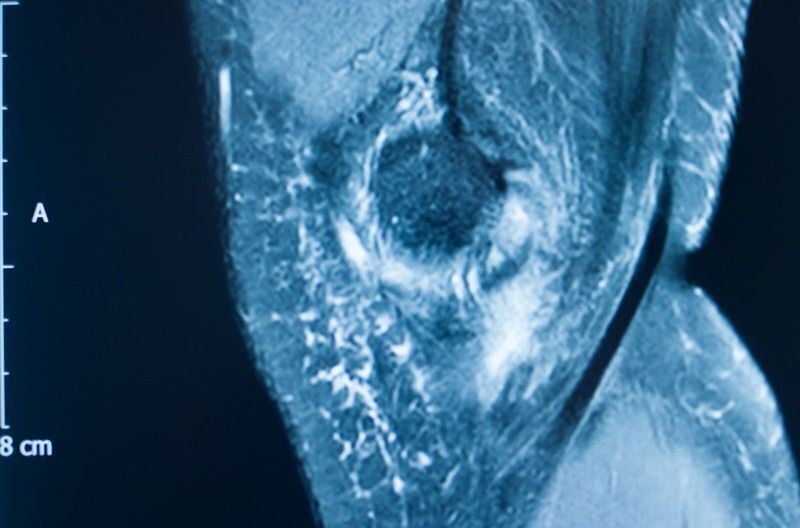

缝线锚钉可用于足部、踝部、膝盖、肩部、肘部、手部和手腕的各种手术。这些设备提供预装和未装配置,整合到熟悉的流程中,并使用标准器械。

这些植入物使用专有的矿物质纤维基质,旨在模仿骨骼的结构特性,同时促进自然骨骼再生和最终的完全整合。与可能干扰成像或导致应力屏蔽的金属不同,与可能过早失去强度的传统可吸收材料不同,OSSIOfiber植入物在愈合过程中保持强度,然后消失——只留下愈合的骨骼。